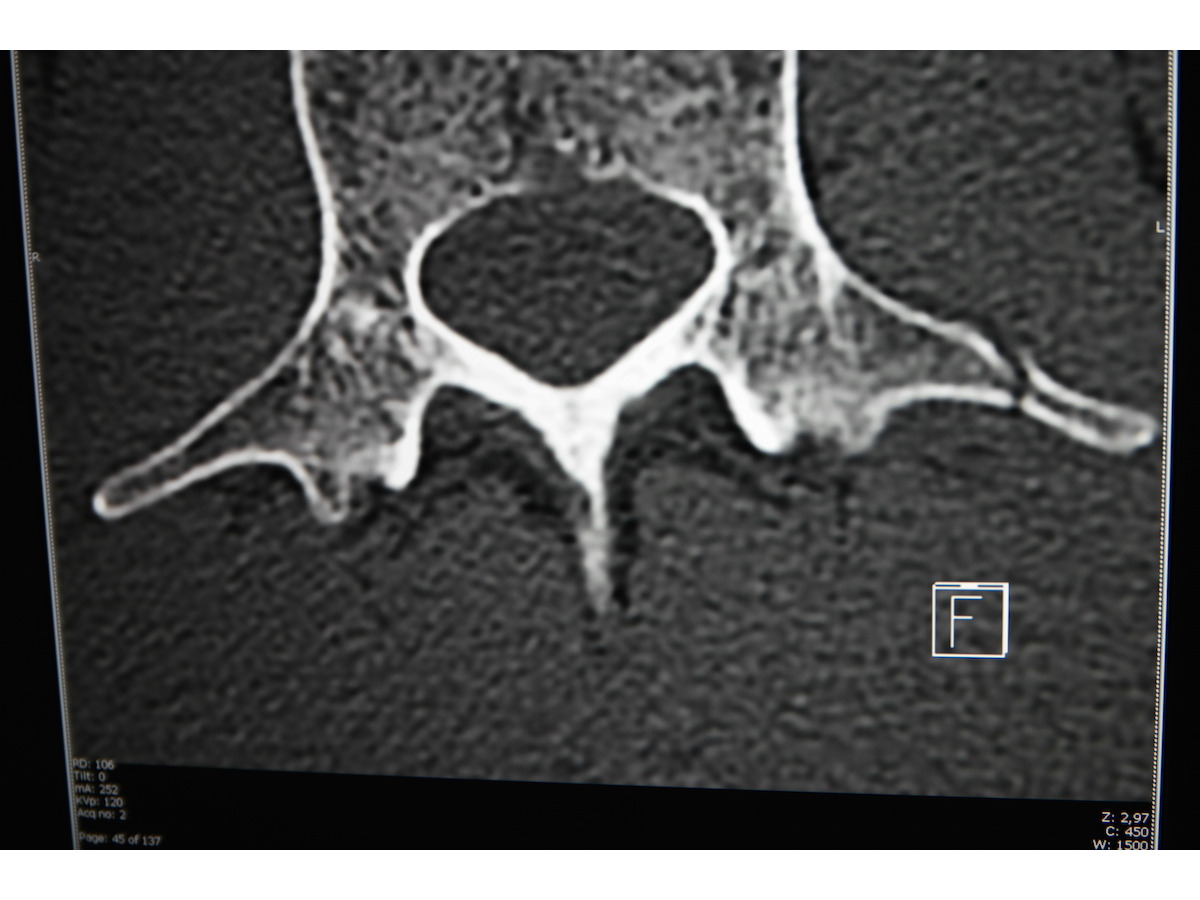

わび さび Misia 落馬骨折 胸椎棘突起 とは 背骨には 7個 頸椎 12個 胸椎 5個 腰椎 に仙骨と尾骨があるそうだ 図にあるように胸椎の 棘 きょく 突起 骨折のようだ Misia Nhk紅白 どうなる Misia News23 撮影中に落馬し骨折 12月の

前後 (1)病態 衝撃の大きい追突や、衝突によるバイク・自転車からの転落で、腰椎横突起骨折は発生しています。 14年のワールドカップでは、ブラジルのネイマールがl3左の横突起骨折で戦列を離れました。 横突起は、腰椎には、l1~l5の椎体の左右に5つ存在しています。口突起骨折の方は突起尖の小さい骨折 (図4b) であり, 転位も少ないので放置し, 鎖骨外側端 骨折のみの固定としたが, 転位の増加もなく無 症状である 2例の鳥口突起単独骨折は何れも16歳の男性 に見られた基部骨折であり, 筋力によるものもおう突起骨折したが、めっちゃ痛いです本当に良くなりますか?痛みはいつ頃無くなりますか?後遺症はありますか?すいませんが教えて下さい。 頭痛・腰痛・肩こり 解決済 教えて!goo

骨折等を、同乗者Aは、骨盤及び腰椎骨折等 を、同乗者Bは、肺 はい 挫傷 ざしょう 及び腰椎横 おう 突起 とっき 骨折等をそれぞれ負った。 (付図1 事故発生経過概略図、写真1 事故発生場所(本件防波 堤) 参照) 気象・海象衝撃の大きい追突や、衝突によるバイク・自転車からの転落で腰椎横突起骨折は発生しています。 腰椎には横突起という骨突起があります。 背筋の中に埋もれており、筋肉の力を腰椎に伝える役目を果たしています。 交通事故やスポーツな金谷 文則ほか(琉球大学) 発行日:15年07月01日 〈抄録〉 橈骨遠位端骨折が解剖学的に整復され,前腕回旋中間位でdrujに不安定性がなければ尺骨茎状突起骨折を内固定する必要はない.不安定性がある場合,先端から中央部の茎状突起骨折ではtfcc損傷の合併が考えられ,tfcc修復術または回外

背骨横突起骨折 普通 で 無難 が丁度良い